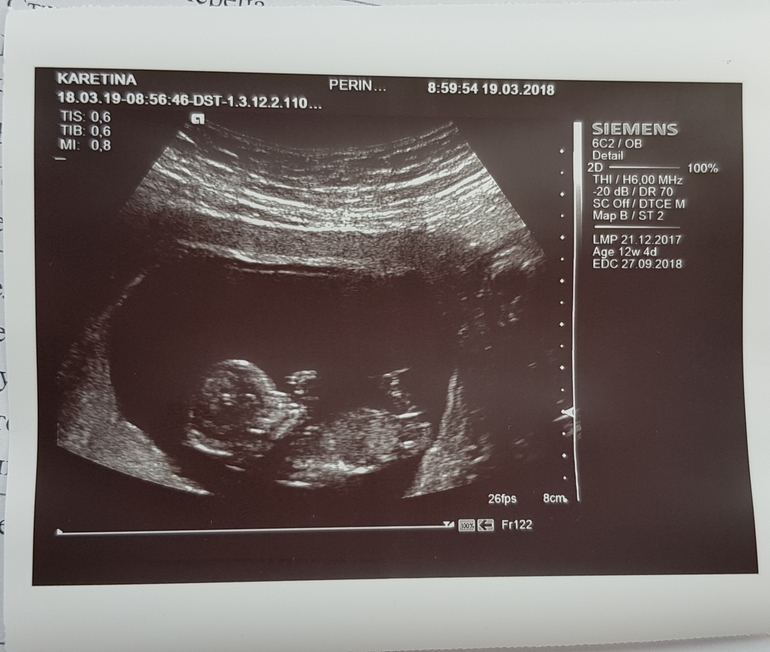

Делают Ли Фото На 1 Скрининге⚡ 👉🏻👉🏻👉🏻 ВСЯ ИНФОРМАЦИЯ ДОСТУПНА ЗДЕСЬ, КЛИКАЙ 👈🏻👈🏻👈🏻Делают Ли Фото На 1 Скрининге